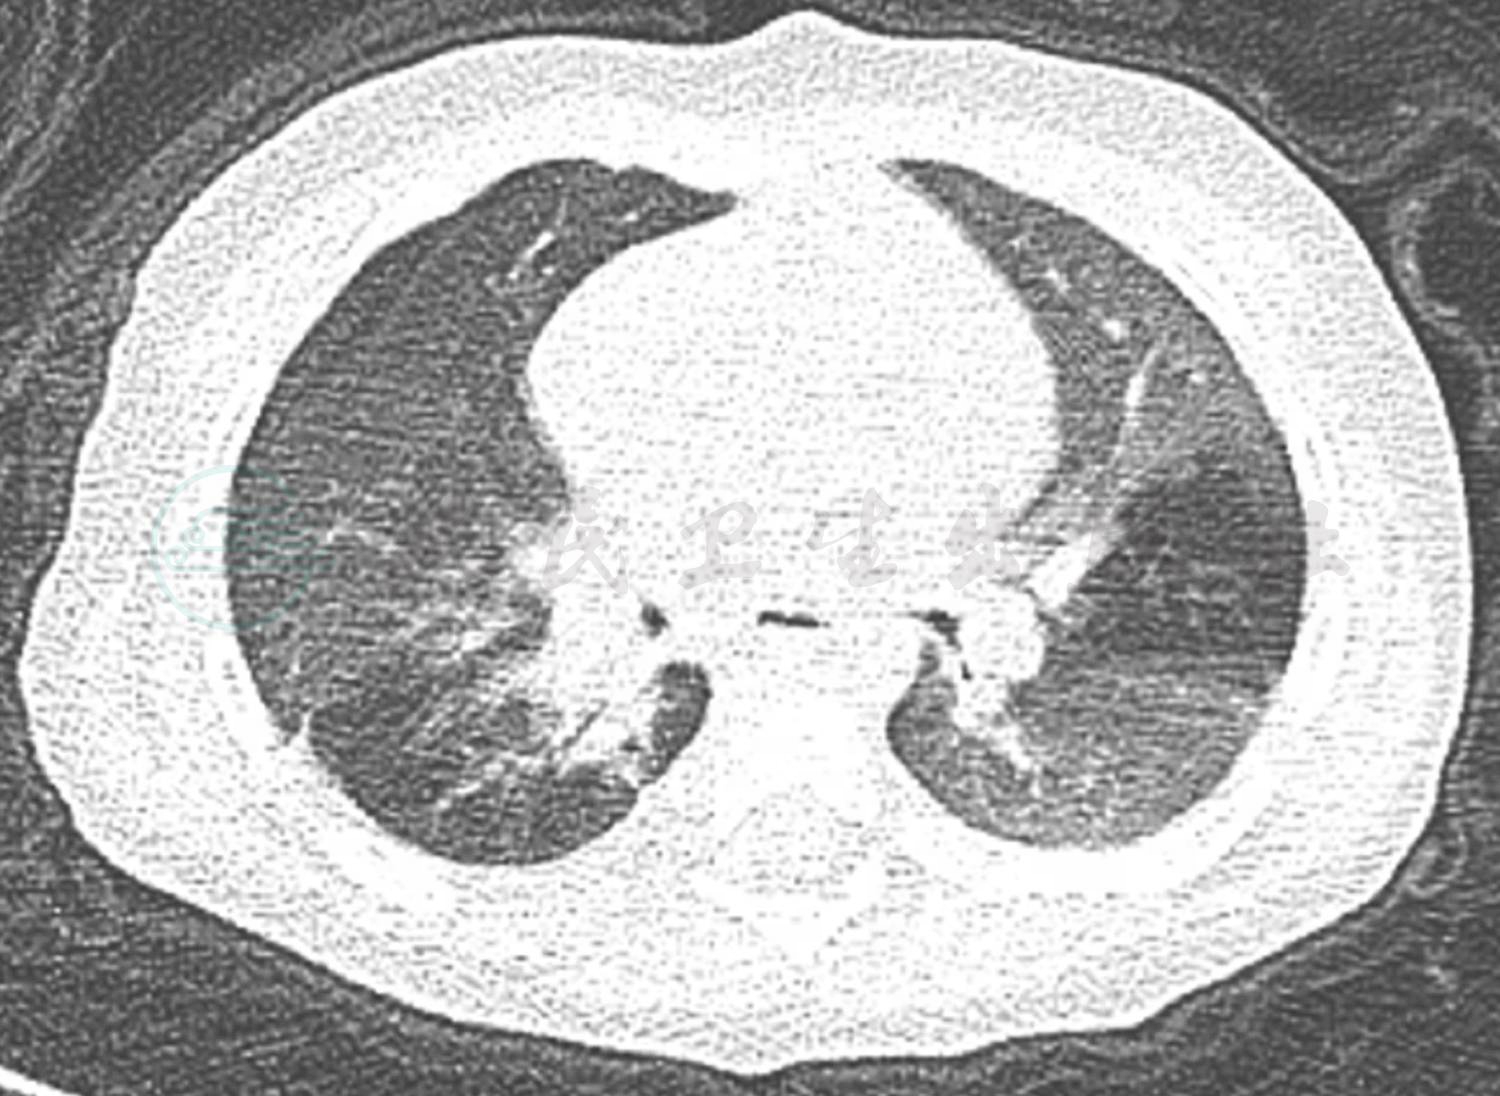

辅助检查:门诊血常规:WBC 10.7×109/L;NE% 37.0%;EO 1.41×109/L;Hb 119g/L;PLT 415 ×109/L。总IgE 5.3U/ml。食物-呼吸过敏原:牛奶、猫毛皮屑过敏。肺CT(图1、图2):双肺野透过度明显不均匀,小气道病变;多叶、段散在炎症,尤以右肺显著,伴右肺支气管显示不佳。

入院后予布地奈德及复方异丙托溴铵泵吸止喘,磺苄西林静脉滴注抗感染治疗。入院第2天化验结果回报:血气离子分析正常,尿、便常规正常,肝肾功能、心肌酶谱正常。CRP 1.46mg/L;结核抗体阴性;肺炎支原体抗体阳性(1:80);肺炎衣原体抗体-IgM阴性;肺炎支原体抗体-IgM阴性;肺炎支原体-DNA测定阴性(建议复查);病毒抗体八项未见明显异常。提示肺炎支原体感染不除外,予红霉素静脉滴注。免疫球蛋白:IGG 6.24g/L(正常4.81~12.21g/L),IGA 0.349g/L(正常 0.42~1.58g/L),IGM 1.38g/L(正常0.41~1.65g/L),IGA略低于正常下限。淋巴细胞亚群:总T细胞 73%(正常55%~84%),T抑制毒细胞44%(正常13%~41%),T辅助细胞23%(正常31%~60%),Th/Ts 0.52(0.71~2.78),NK细胞7%(正常7%~36%),总B细胞12%(正常5%~20%),暂不支持免疫缺陷。入院时肺CT(图1、图2):双肺野透过度明显不均匀,小气道病变,符合儿童哮喘的肺CT改变,但没有明显马赛克征改变,与闭塞性细支气管炎不相符,同时肺CT提示右肺支气管显示不佳,可能为管腔内阻塞:分泌物潴留?支气管异物?或是支气管管腔受压?因此,进一步纤维支气管镜检查成为我们关注的重点。入院第3天予完善纤维支气管镜检查:右主支气管黏膜光滑,略充血水肿,右肺下叶开口处可见黄白色异物(图3),用异物篮将异物取出,异物嵌顿处有大量肉芽组织增生(图4)。右肺上叶开口炎性狭窄明显,左肺各叶段支气管管腔开口通畅未见痰栓堵塞、狭窄及异物征象。异物取出后继续予雾化及抗感染治疗,患儿咳嗽及喘息较前明显缓解。住院治疗第6天,患儿偶有咳嗽,无喘息,肺部听诊无喘鸣音,好转出院。

图2 双肺透过度不均匀,散在炎症,右肺支气管显示不清